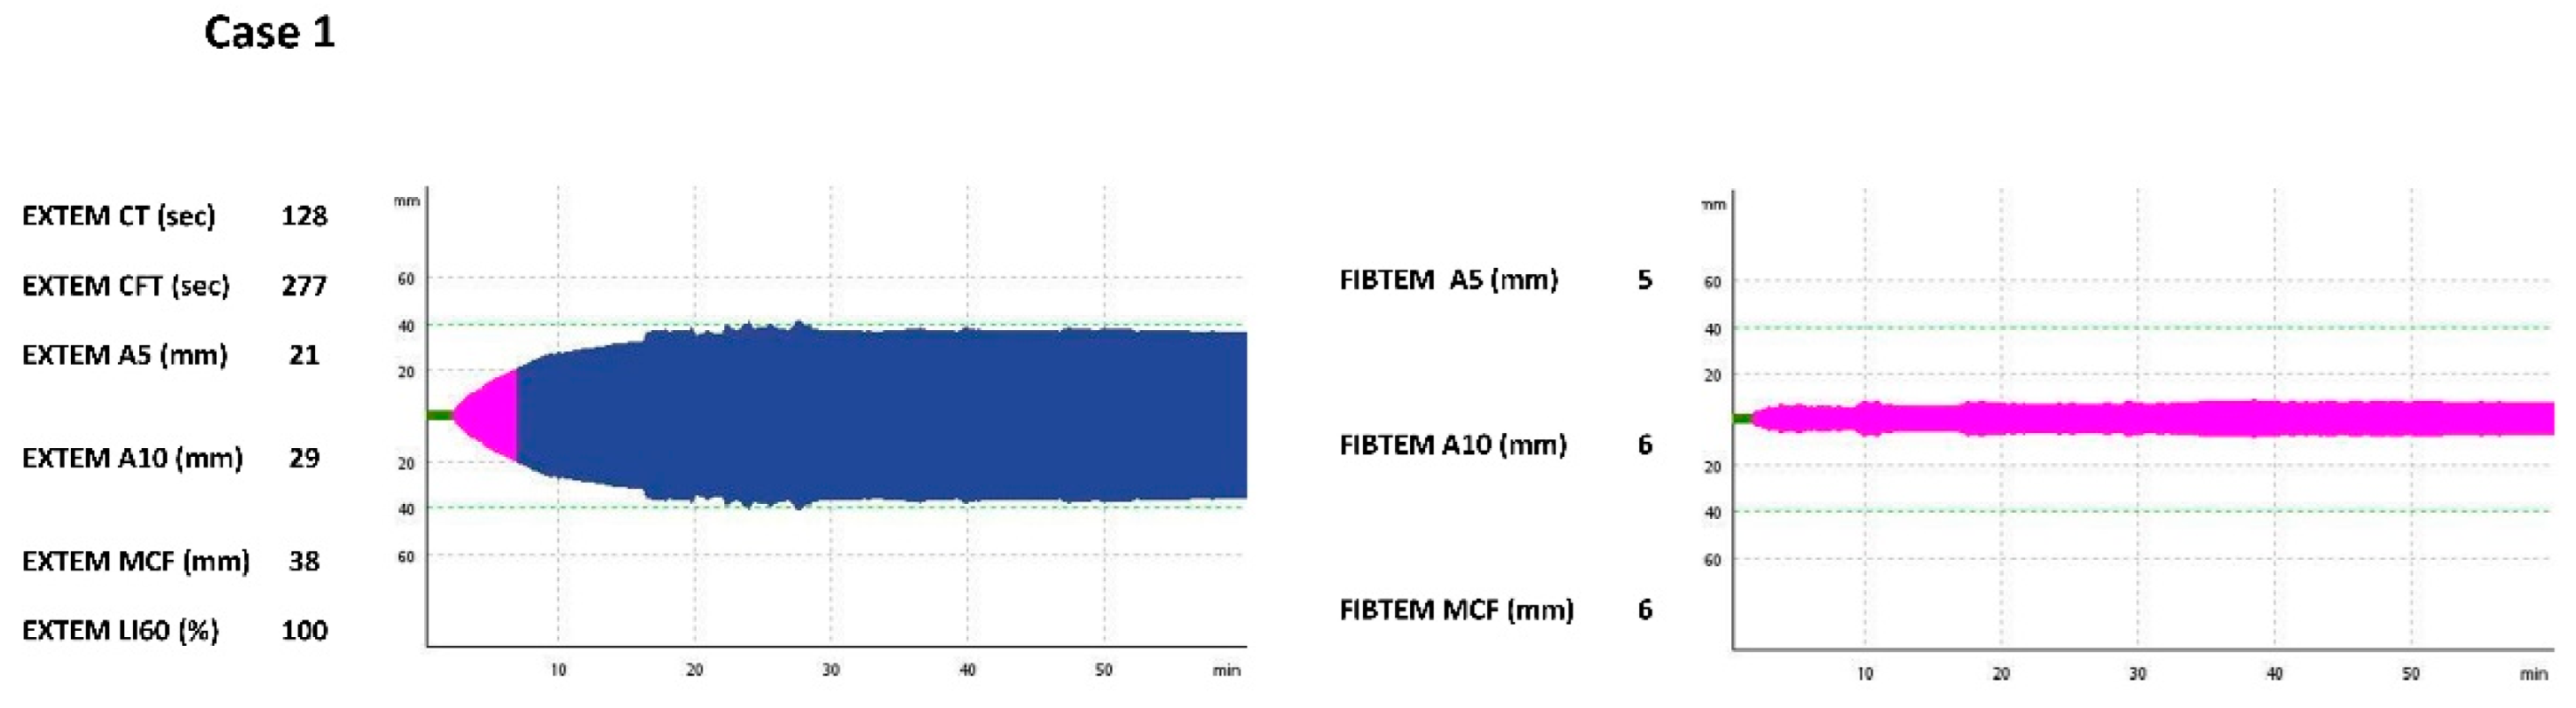

2.1. Case 1

| EXTEM CT (s) | N/A | 128 | 54 | 163 | N/A | 62 |

| EXTEM CFT (s) | N/A | 277 | 190 | 650 | N/A | 87 |

| EXTEM A5 (mm) | N/A | 21 | 26 | 12 | N/A | 42 |

| EXTEM A10 (mm) | N/A | 29 | 37 | 19 | N/A | 53 |

| EXTEM MCF (mm) | N/A | 38 | 48 | 32 | N/A | 58 |

| EXTEM LI60 (%) | N/A | 100 | 100 | 100 | N/A | 98 |

| FIBTEM A5 (mm) | N/A | 5 | 13 | 4 | N/A | 19 |

| FIBTEM A10 (mm) | N/A | 6 | 15 | 4 | N/A | 21 |

| FIBTEM MCF (mm) | N/A | 6 | 20 | 4 | N/A | 26 |